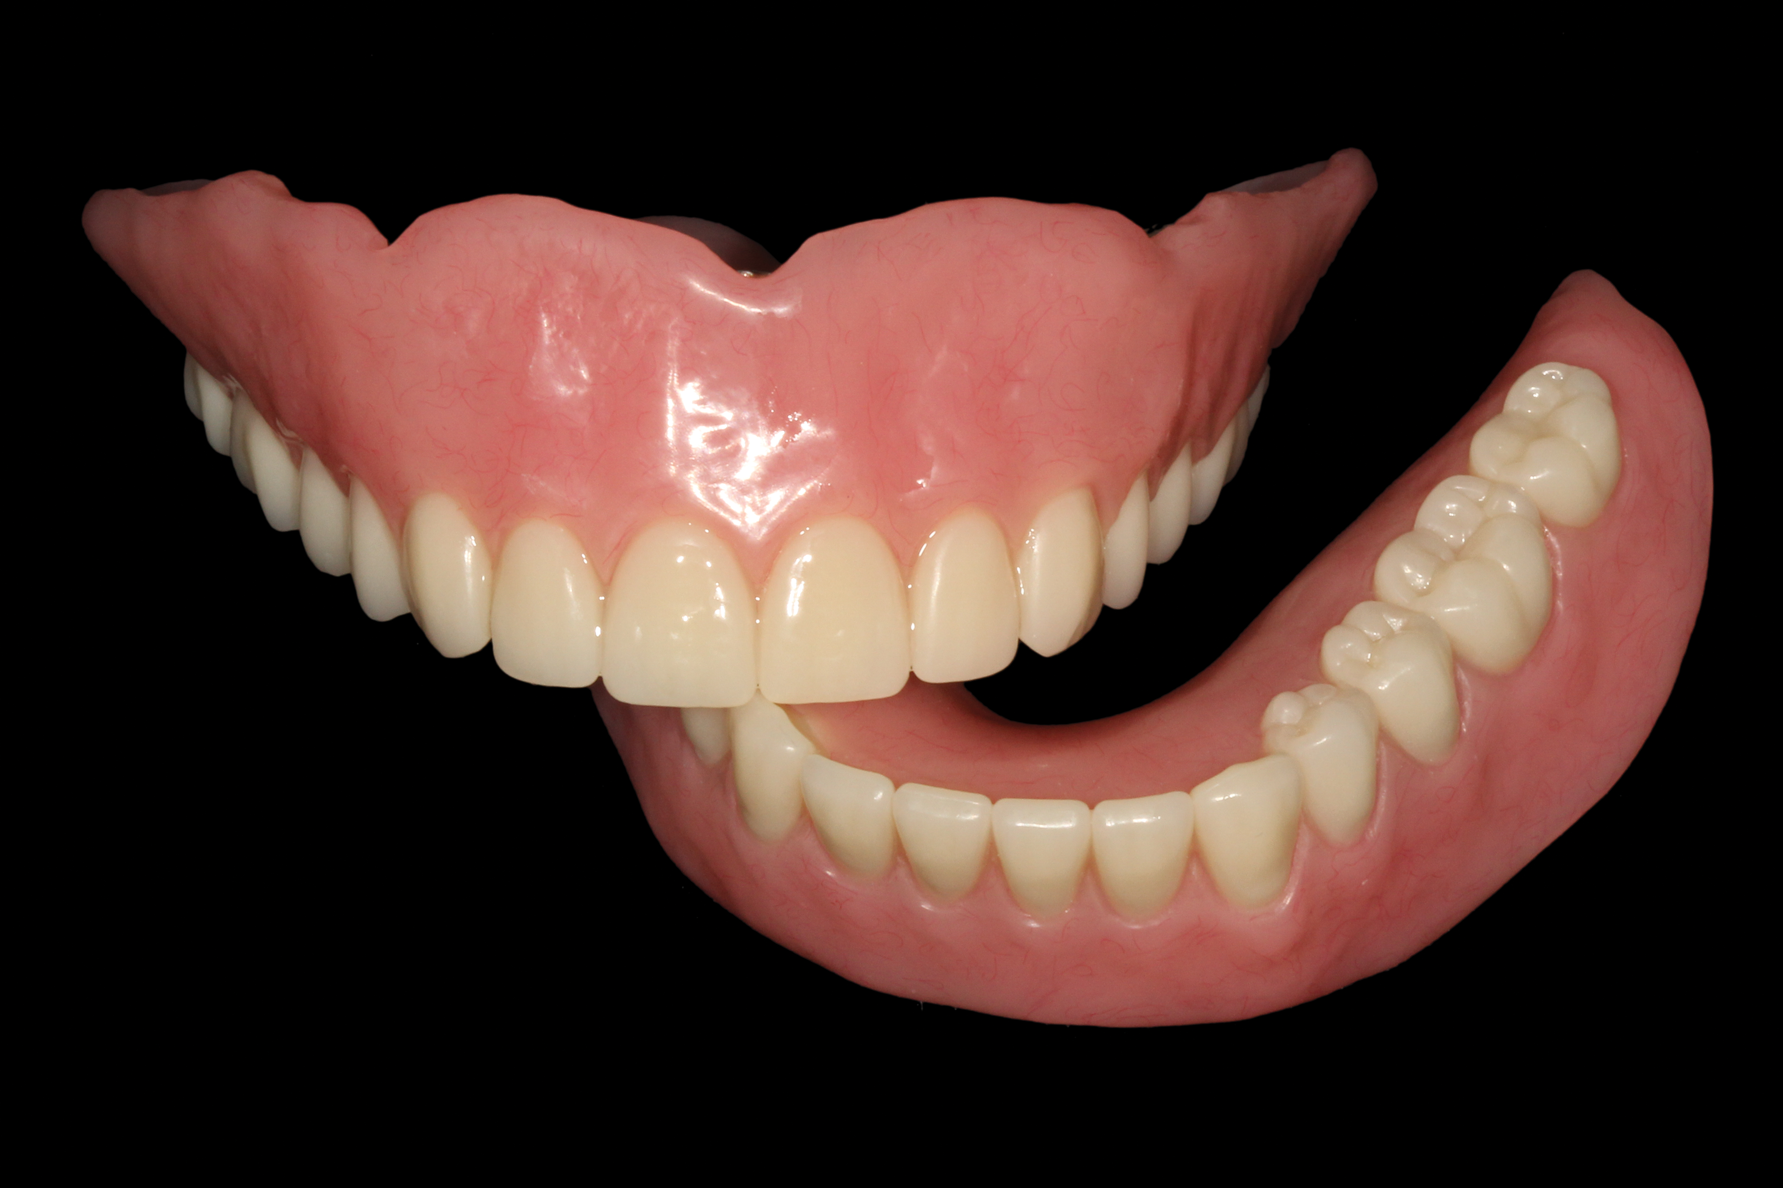

The optical scan files were imported into a dental laboratory planning software (Dental System, 3Shape, [alternatively: DWOS Dental Software, Straumann Group; DentalCAD, exocad]) and overdenture frameworks were designed (Figure 8). The framework designs were sent to a dental laboratory for 3D printing the frameworks in cobalt-chrome. Using the existing interim dentures as a guide, denture teeth (Pala® Mondial®, Kulzer, [alternatively: Veracia SA, Shofu; SR Vivodent®, Ivoclar Vivadent]) were placed onto the completed frames and assessed with the patient approving the final esthetics and tooth arrangement (Figure 9). The prostheses were completed using conventional acrylic processing techniques.

Fig 9. Complete overdenture prostheses using acrylic resin and denture.

Figure 9